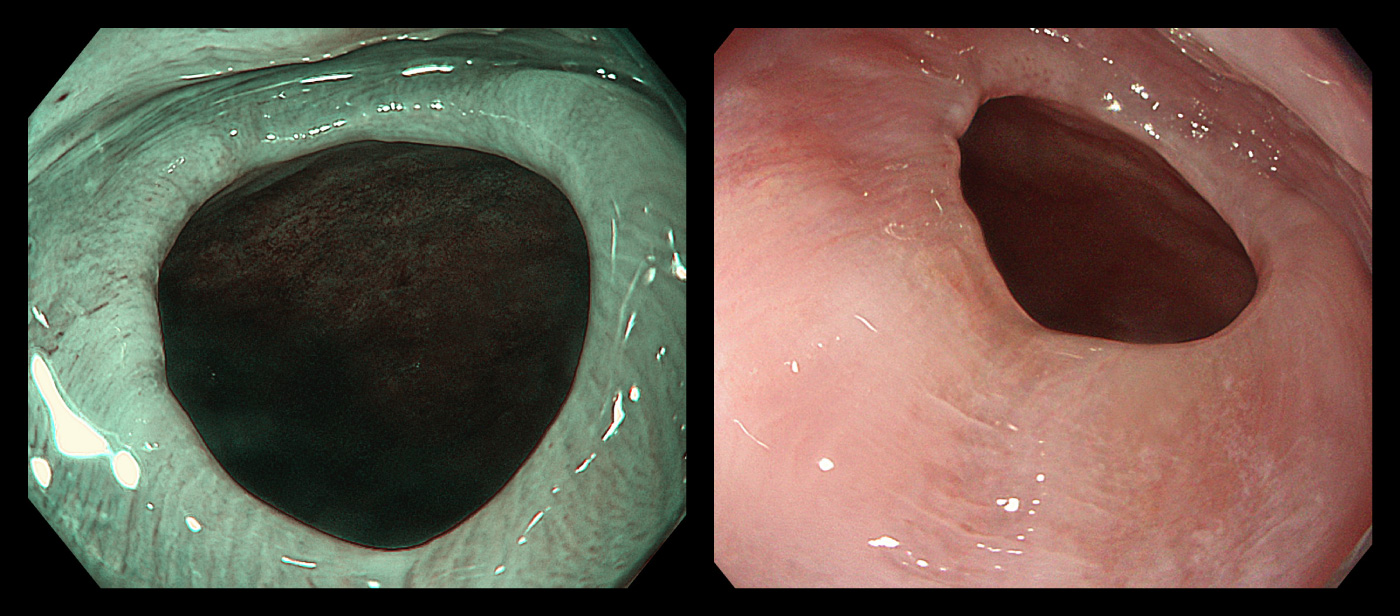

胃アニサキス

ひどい腹痛で受診され、緊急内視鏡で摘出して軽快されました。